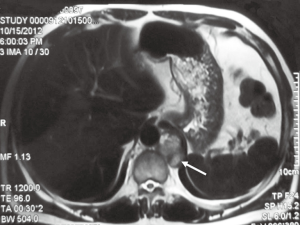

A 48-year-old man was admitted to our center for a functional posterior mediastinal paraganglioma on the left side of the vertebrae. He suffered from hypertension for nine years with intermittent palpitation and headaches without significant family history. The tumor was found incidentally on abdominal computed tomography (CT) scan two months before admission. He underwent surgical exploration via open thoracotomy in another hospital previously. However, his blood pressure increased to 302/165 mmHg when touching the tumor and the operation was terminated. After previous surgery, plasma test of catecholamines showed that norepinephrine was 839 ng/L (ref range, less than 559 ng/L) and epinephrine was 2,340 ng/L (ref range, less than 122 ng/L). He was diagnosed as functional mediastinal paraganglioma and transmitted to our department later. Chest magnetic resonance imaging (MRI) scan was performed and revealed a 2 cm × 3 cm paravertebral mass centered at T11-T12 without vertebrae destruction (Figure 2). Abdominal contrast CT scan showed no abnormalities of the adrenal glands or the retroperitoneum. The patient was medicated with oral alpha- and beta-blockades, as well as intravenous Ringer’s solution (40 mL/kg/day) for two weeks. His hypertension was stabilized and a complete resection of the tumor was planned, using the thoracoscopic approach.